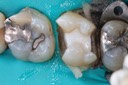

Scott Kanamori #31 pre-op

Scott Kanamori #31 amalgam removal